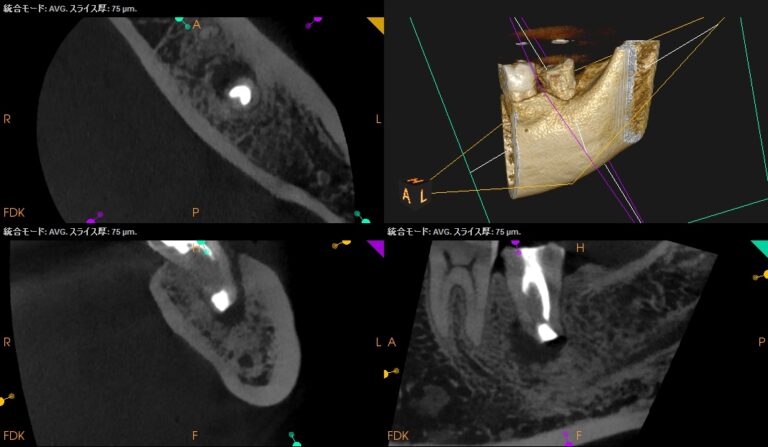

5年前から歯茎にできものができてすごく痛かった…他の歯科医院ではインプラントを計画されたが嫌だ!〜#18 Intentional Replantationと口腔外でのCore build up, 1M recall, 2M recall

紹介患者さんの治療。 主訴は、 5年前から歯茎にできものができてすごく痛かった。5年間ずつと同じ歯の治療をしている…その後、歯ブラシで歯を磨くと痛く、別の歯科医院ではインプラントを計画されたが嫌だったので、かかりつけ医に … 続きを読む 5年前から歯茎にできものができてすごく痛かった…他の歯科医院ではインプラントを計画されたが嫌だ!〜#18 Intentional Replantationと口腔外でのCore build up, 1M recall, 2M recall